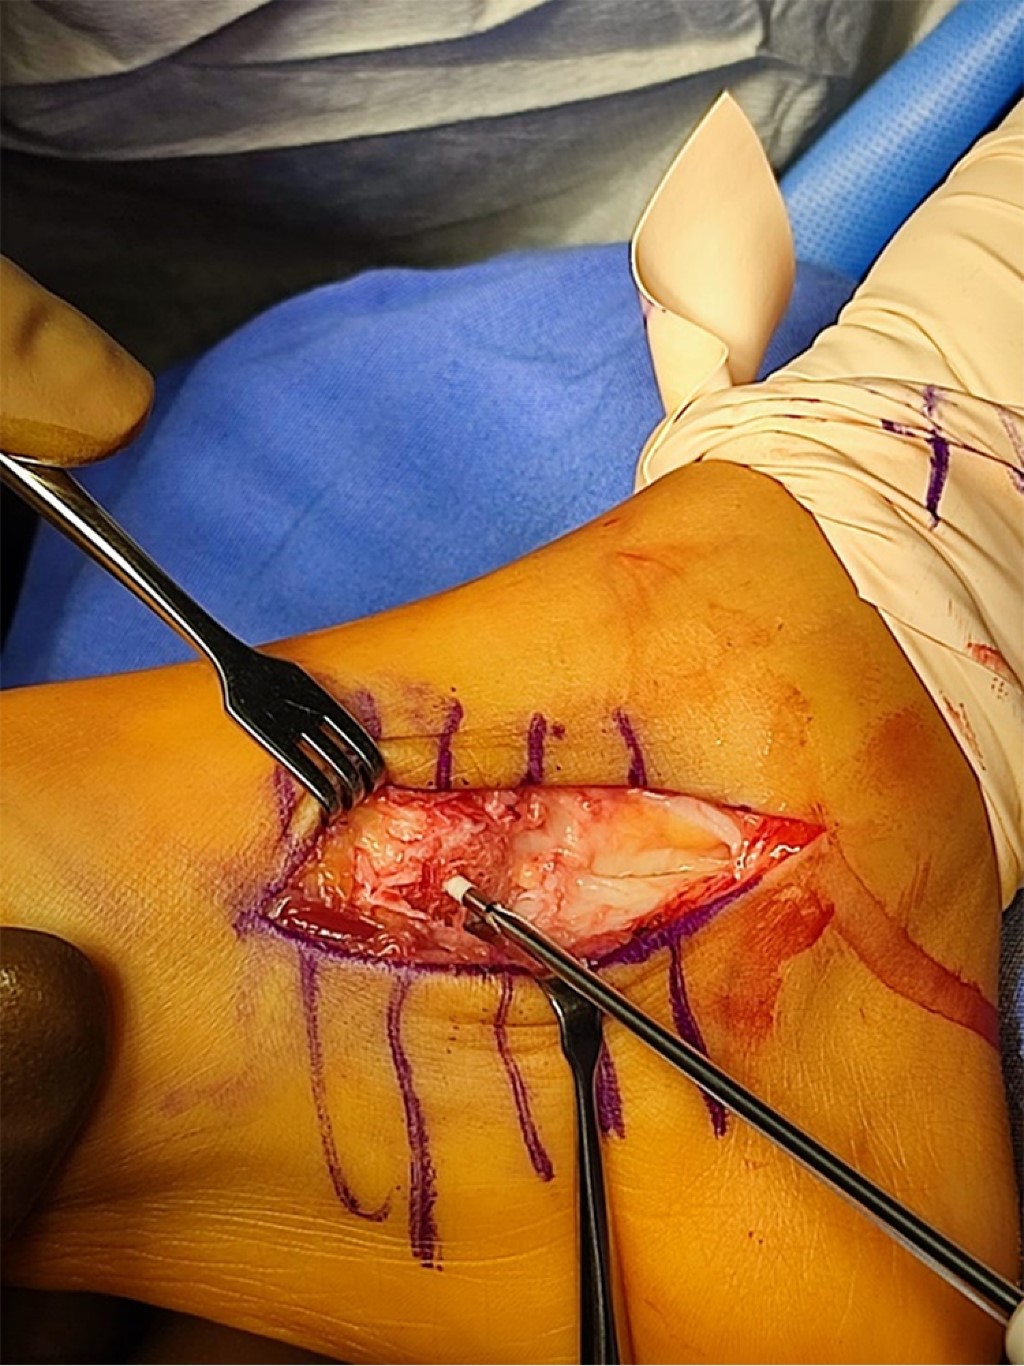

TéCNICA QUIRúRGICA

Se realizó abordaje dorsomedial de 6 cm en cara medial de mediopié a nivel de escafoides, disección del retináculo medial, capsulotomía, desinserción del tibial posterior, resección en la base y reinserción con ancla SutureTak 2.4 mm en escafoides verdadero (Figura 3), colocación de fibra de vidrio suropodálica. La fibra se retiró a las cuatro semanas y se le indicó el uso de zapato ortopédico durante dos semanas, sin requerir rehabilitación.

Figura 3